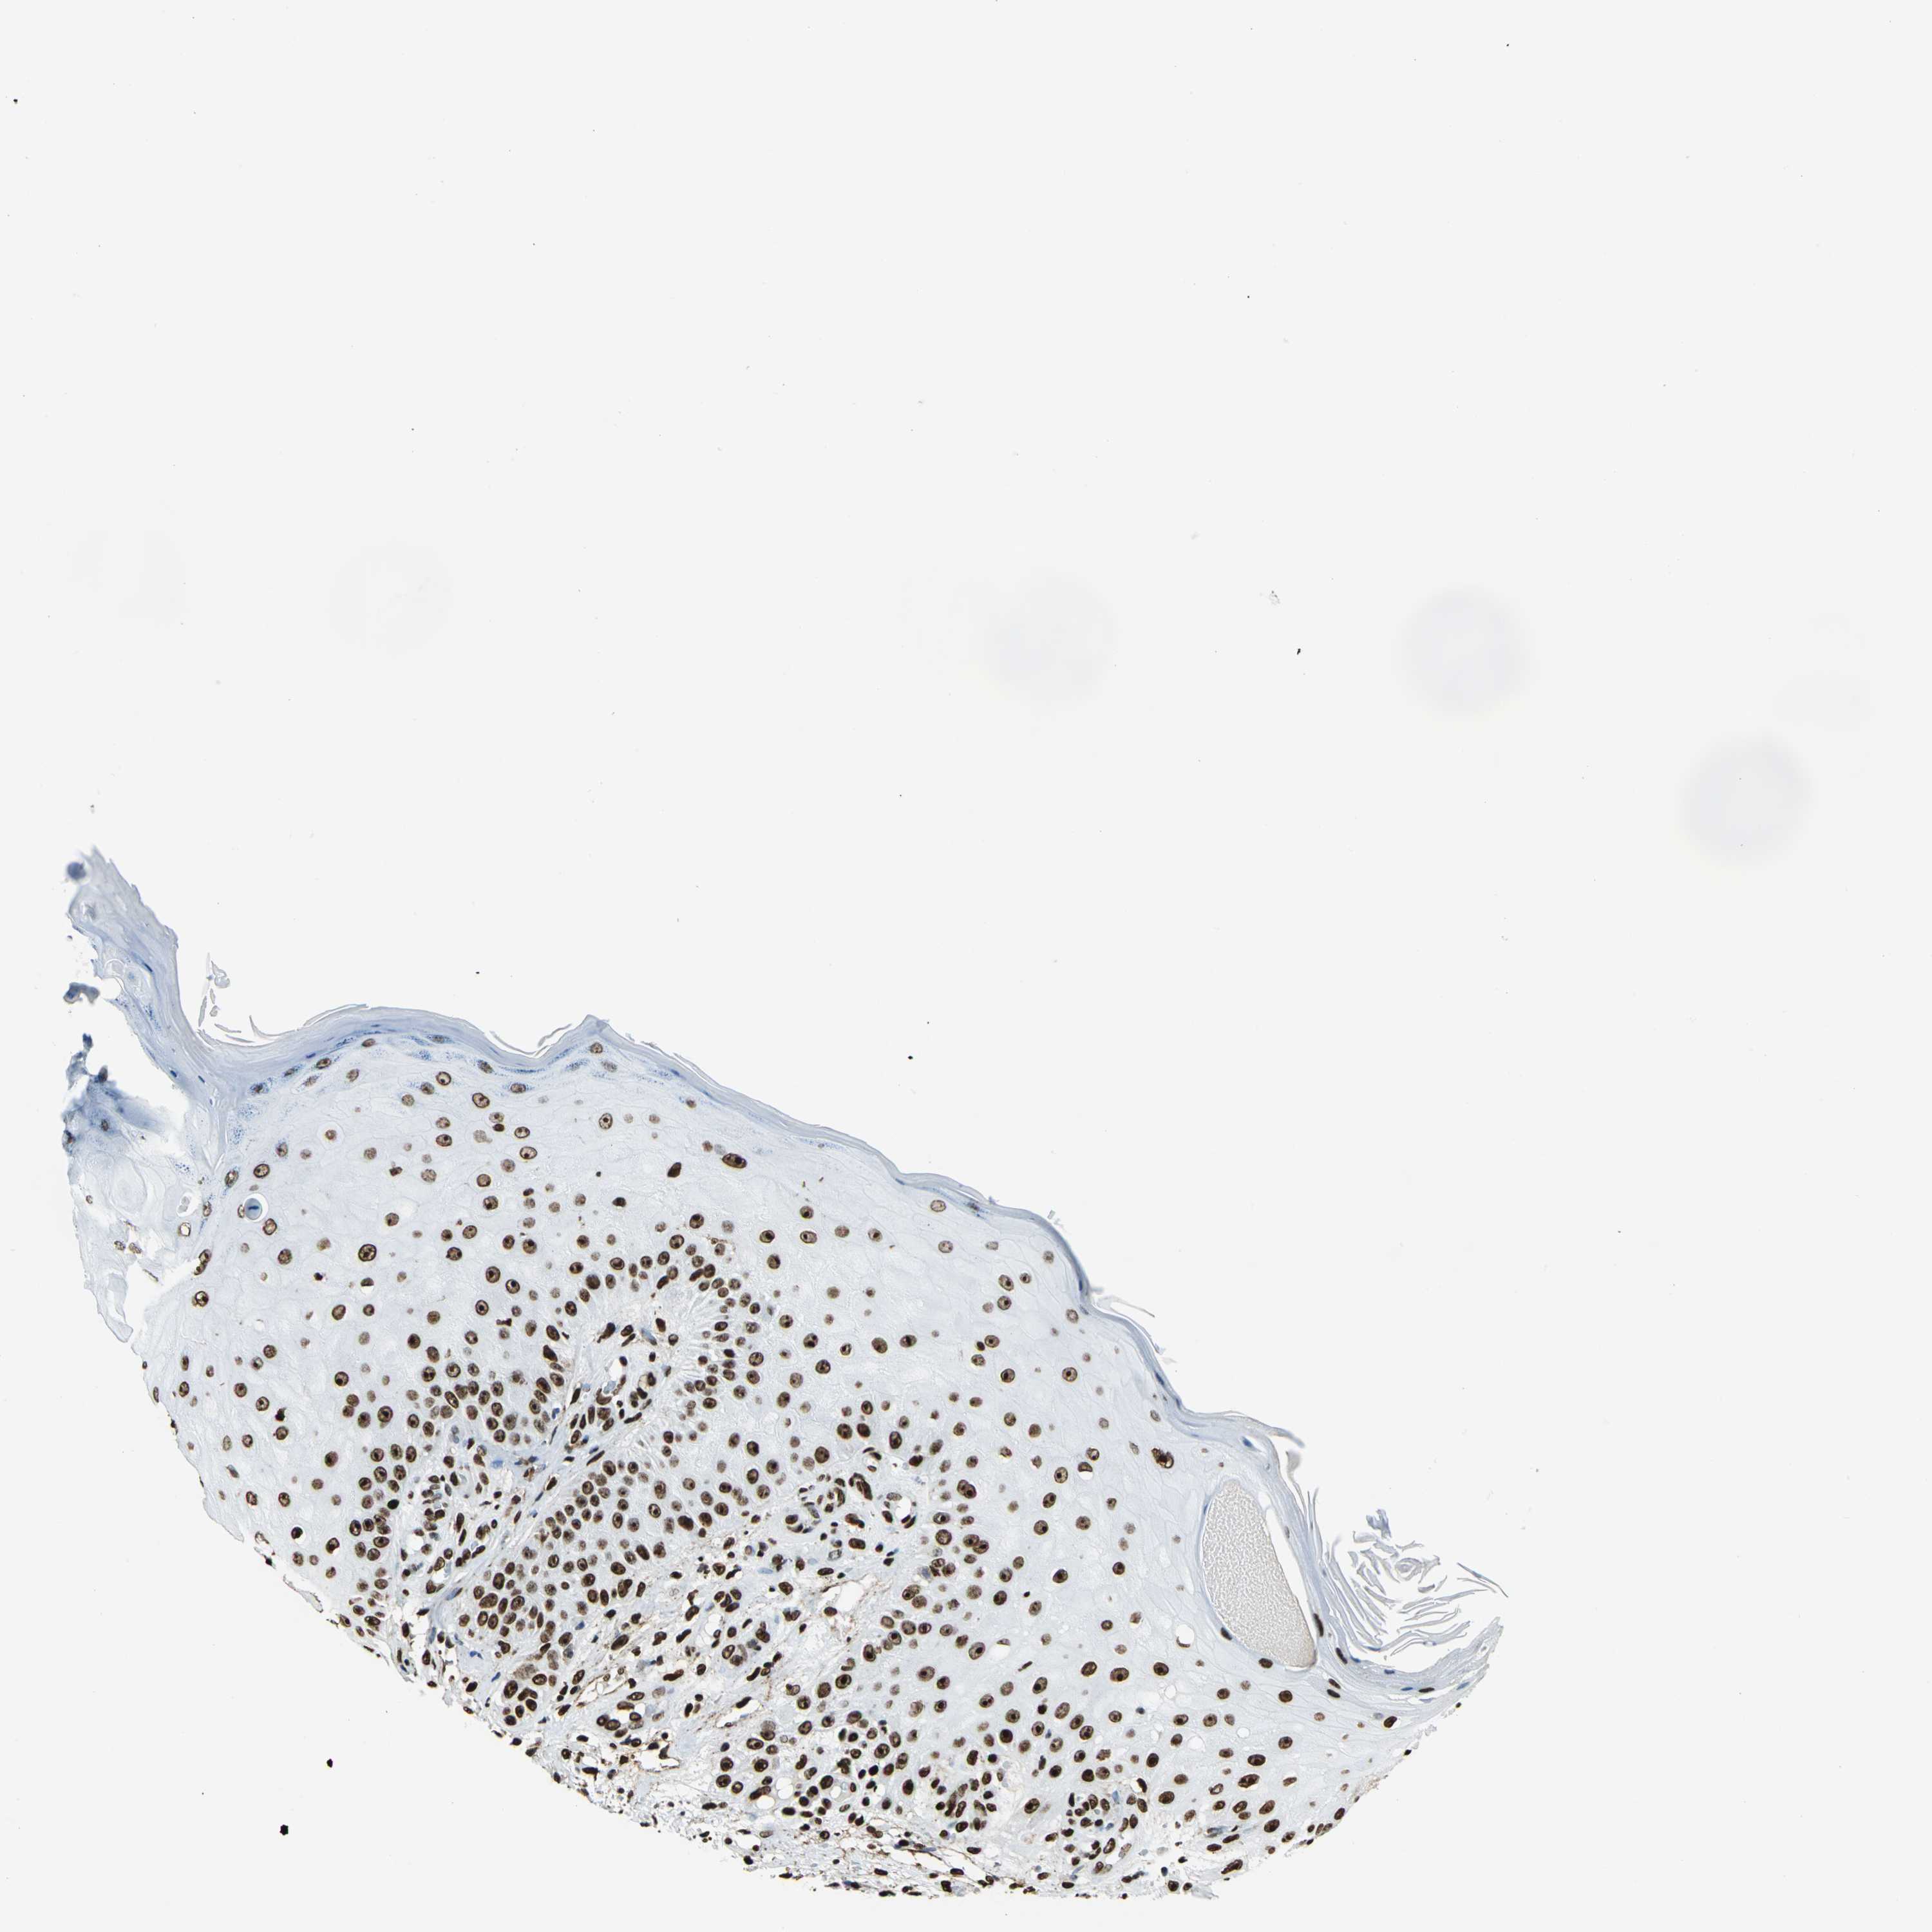

SKIN CANCER - Protein expressioni

A mouse-over function shows sample information and annotation data. Click on an image to view it in a full screen mode. Samples can be filtered based on level of antibody staining by selecting one or several of the following categories: high, medium, low and not detected. The assay and annotation is described here.

Each image is clickable and will lead to virtual microscopy that enables deeper exploration of all samples and also displays staining intensity scores, fraction scores and subcellular localization as well as patient and tissue information for each sample.

Antibody HPA002564

Staining

High

Medium

Low

Not detected

Intensity

Strong

Moderate

Weak

Negative

Quantity

>75%

75%-25%

<25%

None

Location

Nuclear

Cytoplasmic/membranous

Cytoplasmic/membranous,nuclear

Squamous cell carcinoma, NOS